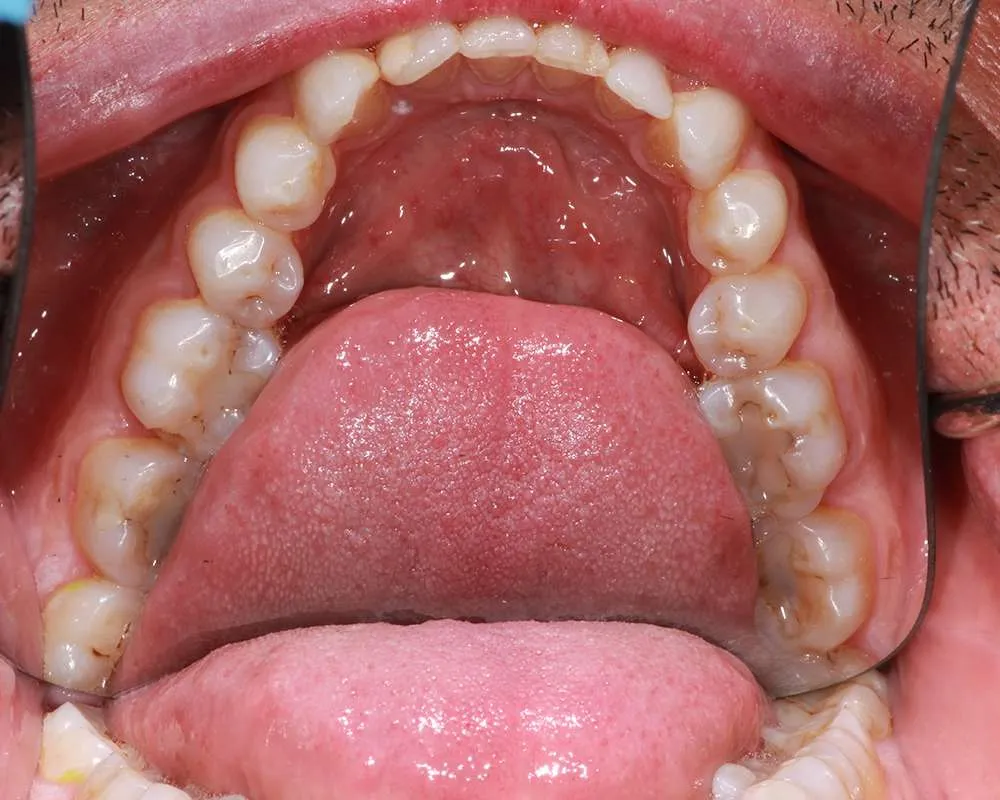

Complex Cases

Witness the Remarkable Changes We Can Achieve

The safe removal of mercury fillings is crucial for your health and well-being. At our practice, we follow strict protocols to ensure that mercury amalgam fillings are removed safely and effectively.